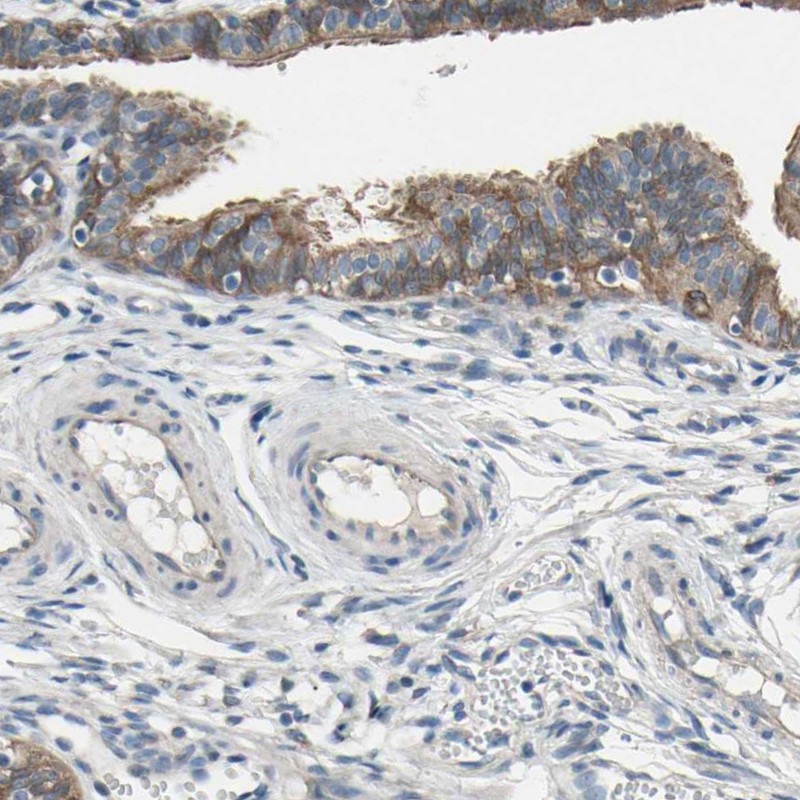

Immunohistochemistry analysis in human fallopian tube and testis tissues using Anti-GRAMD3 antibody. Corresponding GRAMD3 RNA-seq data are presented for the same tissues.